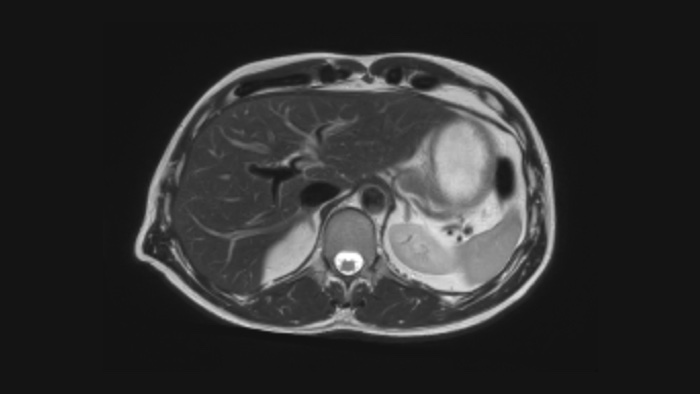

Confianza diagnóstica Ofrece una resolución espacial hasta un 60% más alta en el mismo tiempo de escaneo. 4

Confianza diagnóstica Amplíe su capacidad de obtener imágenes excelentes en todas las áreas clínicas. Vea cómo se benefician sus compañeros.